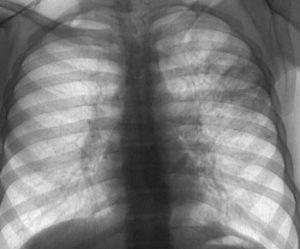

Сложность заключается в том, что выявить плеврит без устранения основного заболевания практически невозможно. Даже на рентгеновском снимке плевральное скопление экссудативной жидкости будет выглядеть как темное пятно, что может быть ошибочно интерпретировано как туберкулезное поражение легких.

Диагностические процедуры включают исключительно инструментально-аппаратные исследования. Пациенту назначают рентгеноскопию в различных проекциях для определения характера патологии и выявления ее первопричины.

Если осумкованный плеврит находится на поздней стадии, дополнительным методом диагностики становится компьютерная томография. Эта процедура схожа с рентгеноскопией, но предоставляет возможность получить более детализированные изображения.

Осумкованный плеврит – это серьезное и сложное заболевание, которое становится опасным только в запущенных случаях. Для раннего выявления этой болезни рекомендуется регулярно проходить флюорографию легких и рентгеноскопию дыхательных путей.